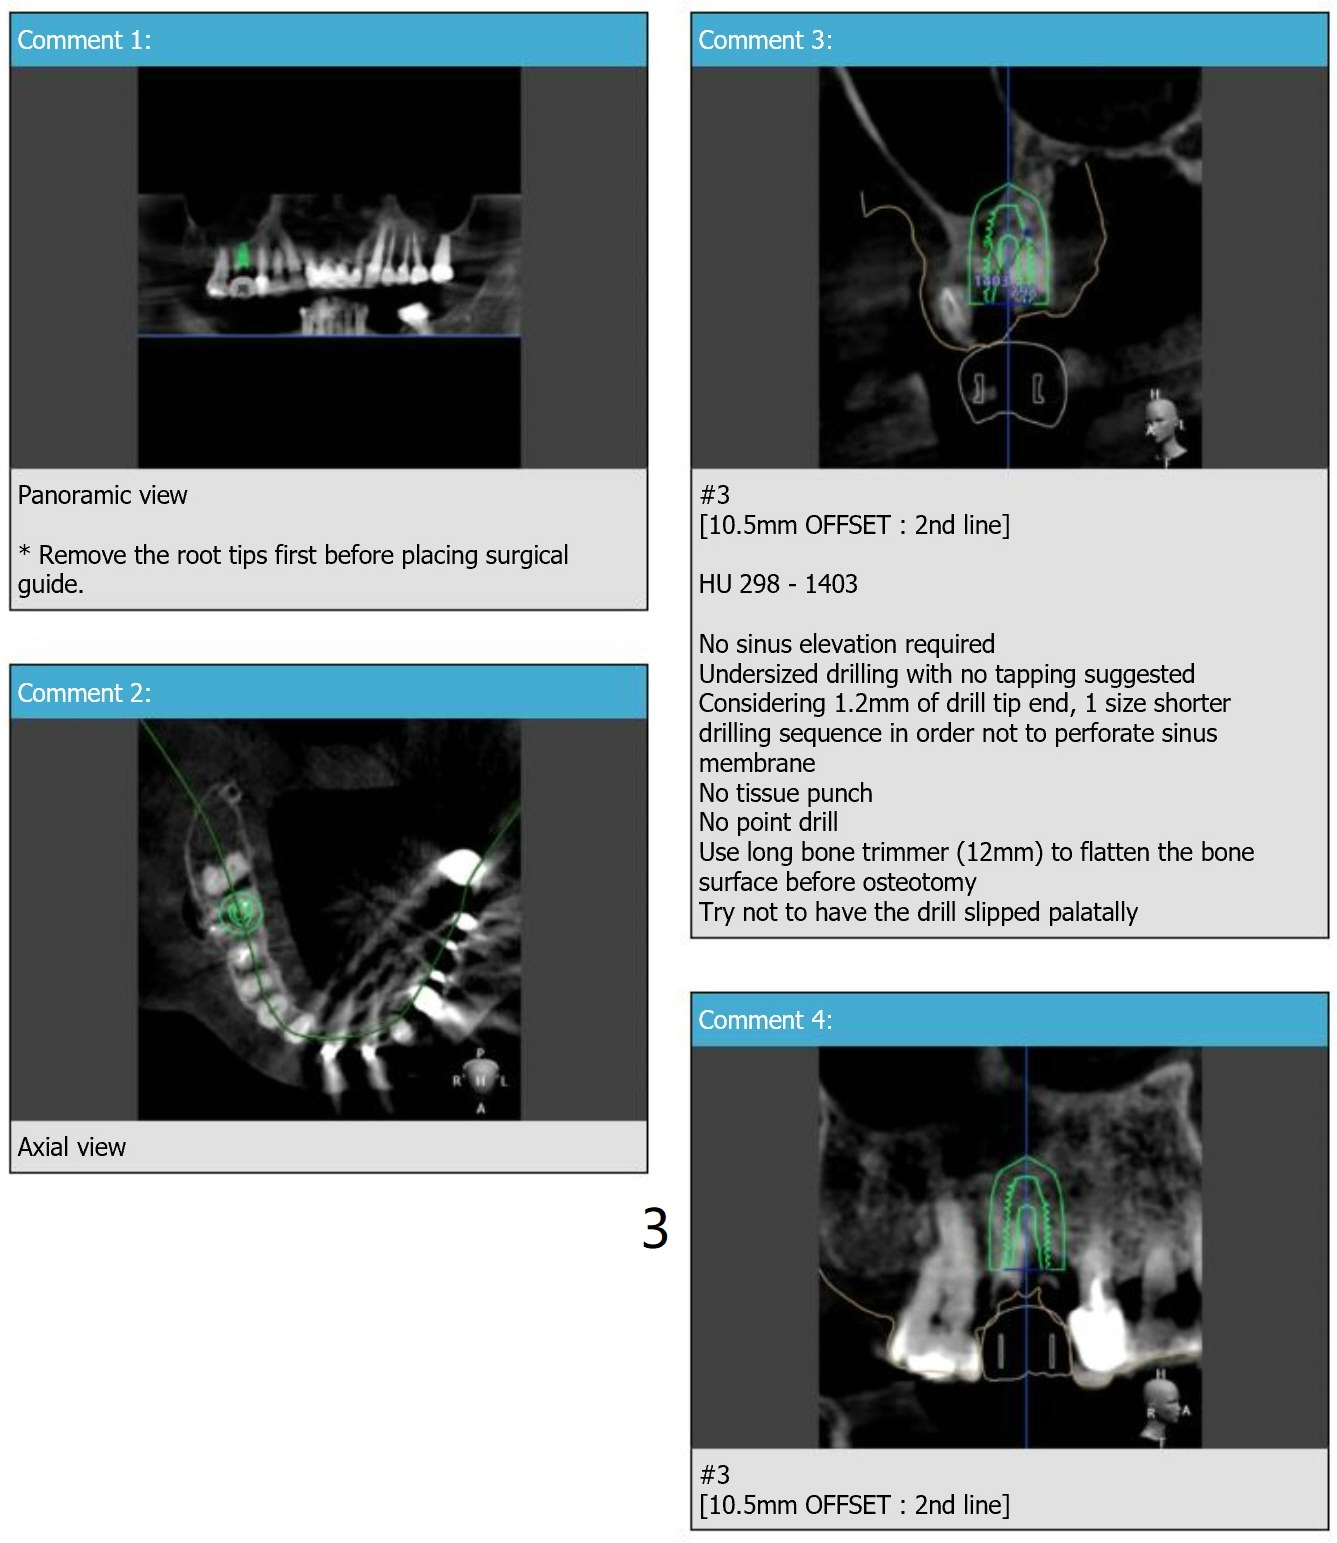

Long Bone Trimmer for #3

Immediate Implant

Molar Immediate Implant,

Prevent Molar Periimplantitis (Protocols,

Table),

Trajectory,